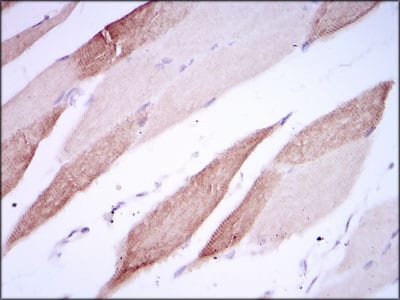

- Immunohistochemical analysis of paraffin-embedded human striated muscle tissues using AlCAM mouse mAb with DAB staining.